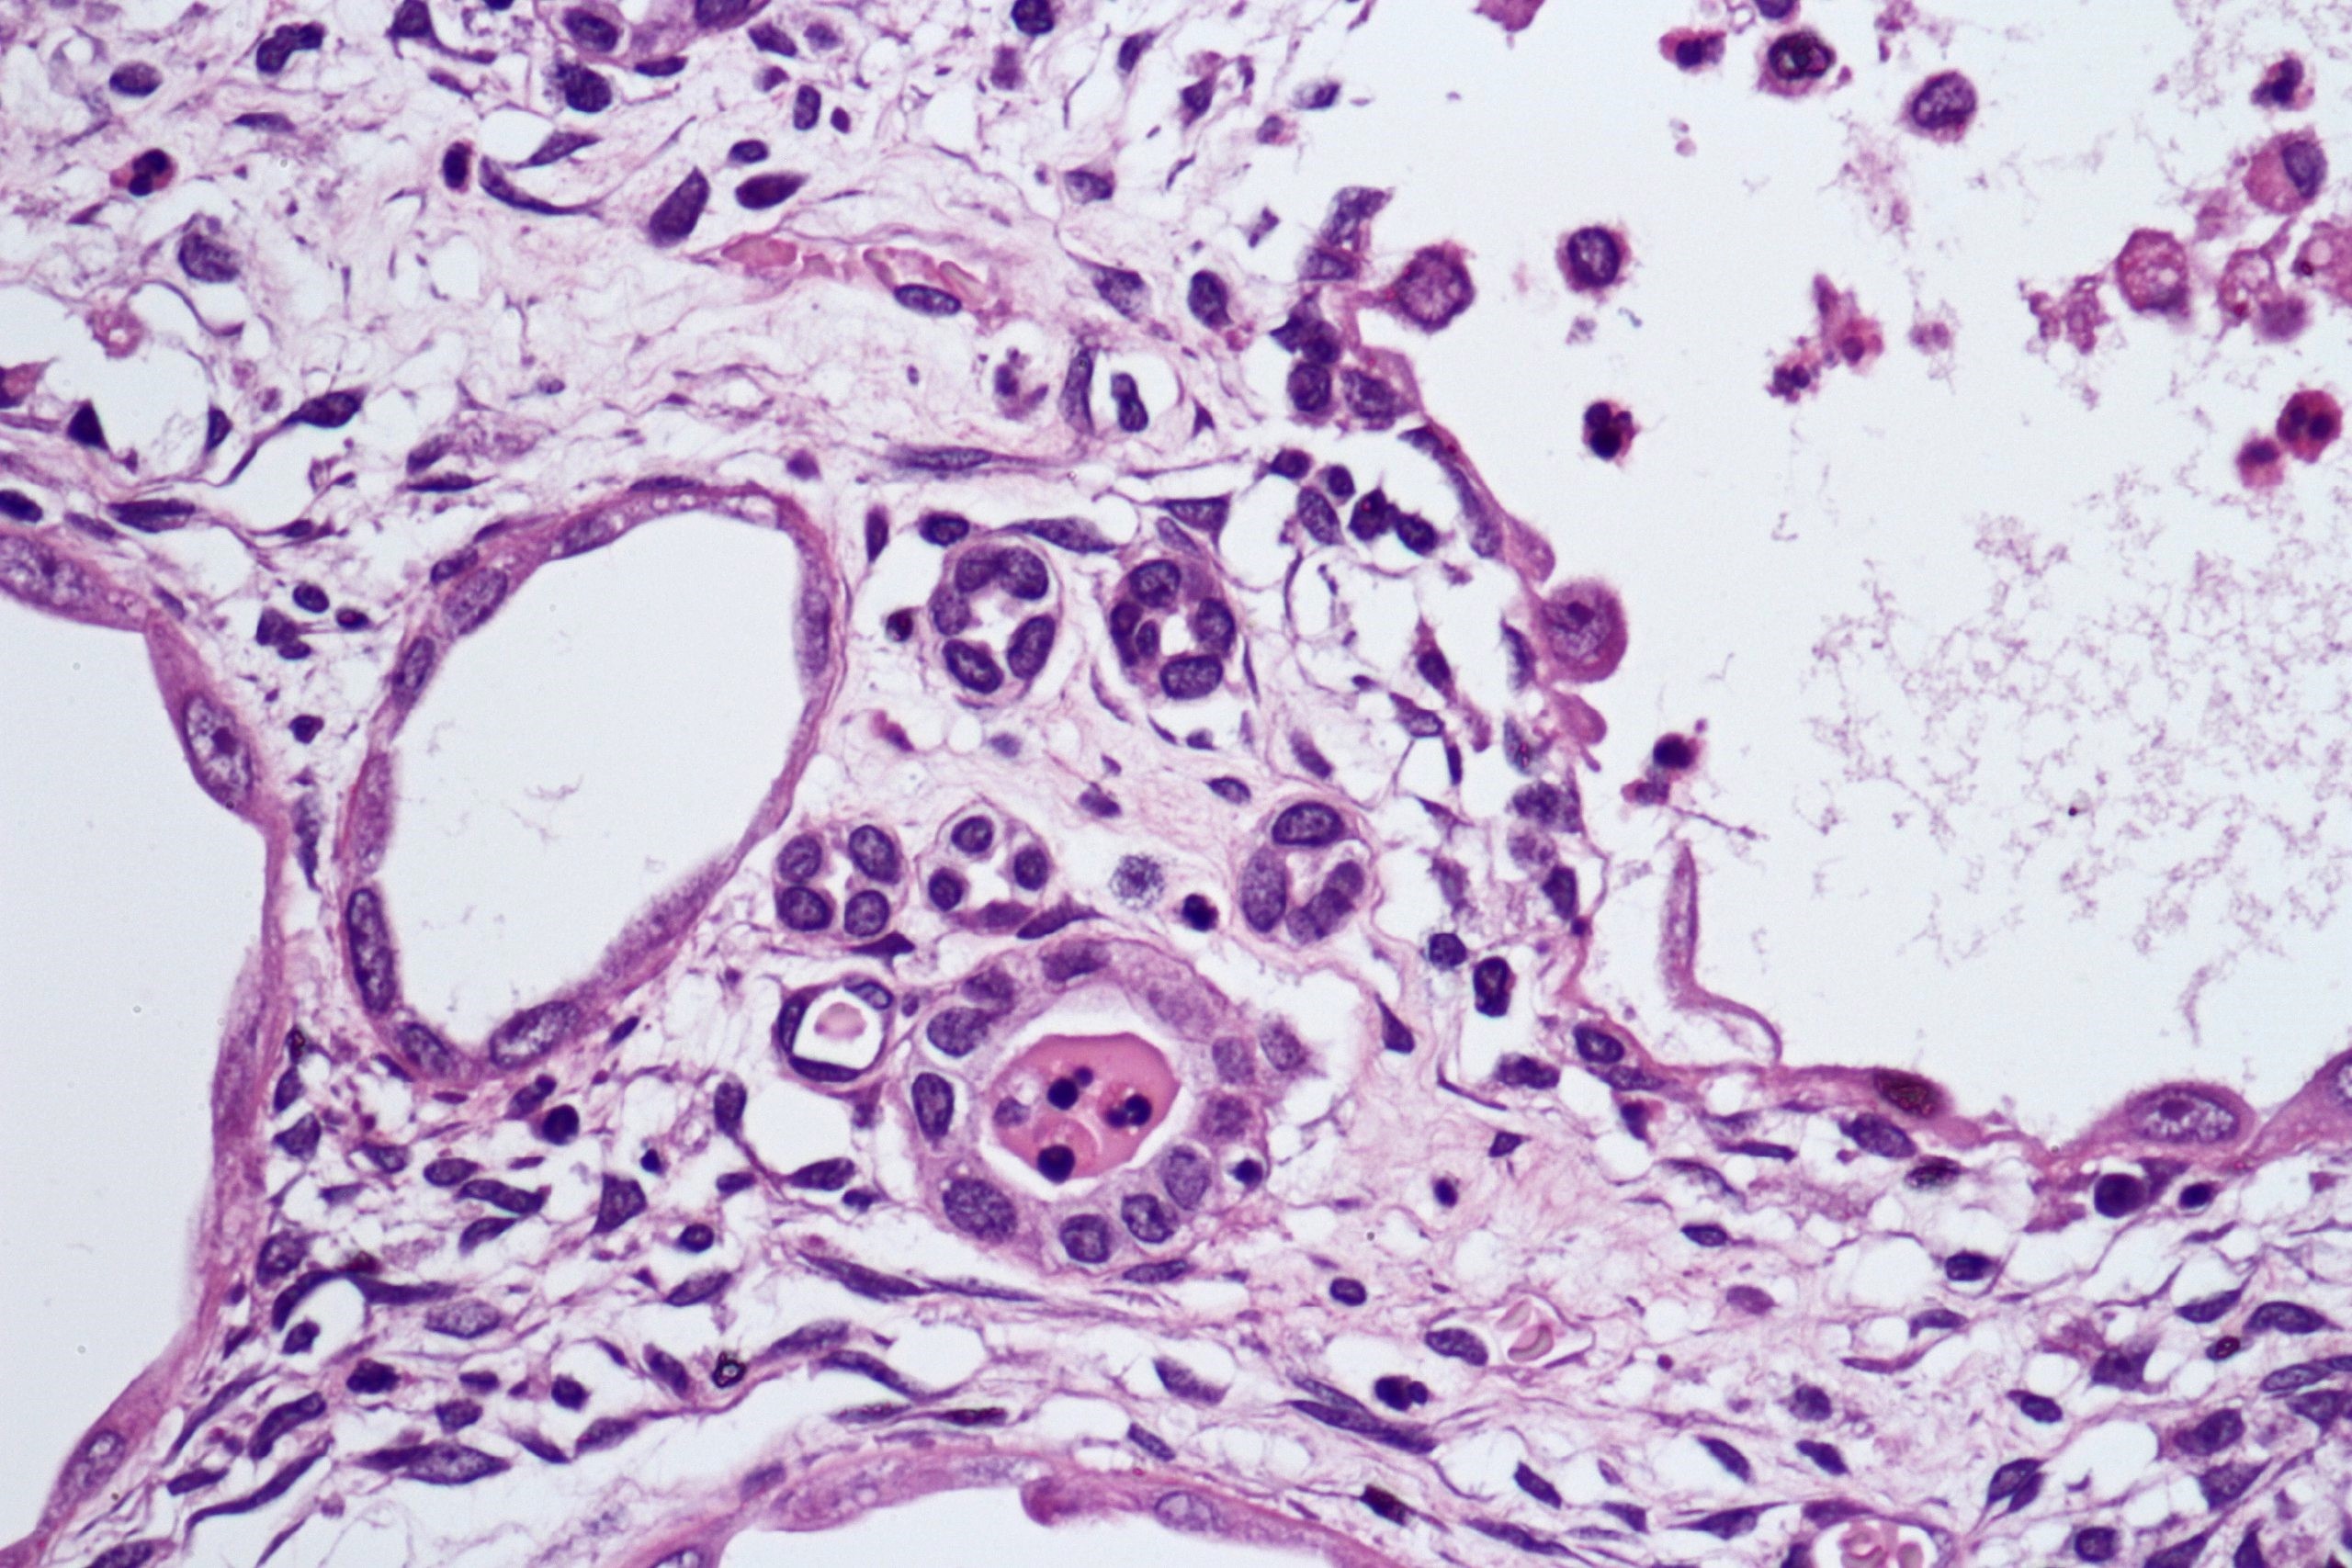

Microscopic (histologic) description

- Cysts lined with flat / cuboidal / hobnail cells (or are denuded)

- Epithelial elements consist mainly of mature and immature / abortive tubules and small papillae resembling immature glomeruli

- Key histological findings of the variably cellular septa include

- Nephroblastomatous epithelial elements

- Islands of undifferentiated blastema and differentiated mesenchymal elements (skeletal muscle and less often cartilage and fat) (J Urol 2010;183:1585)

- Focally, the septal elements may protrude into the cystic spaces in microscopic papillary folds

Microscopic (histologic) images

Contributed by Americo Brilhante, M.D. and Daniel Athanazio, M.D., Ph.D.